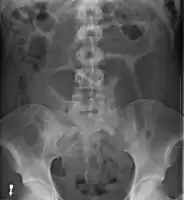

After taking a thorough history, the diagnosis of colonic volvulus is usually easily included in the differential diagnosis. Abdominal plain x-rays are commonly confirmatory for a volvulus, especially if a "bent inner tube" sign or a "coffee bean" sign are seen. These refer to the shape of the air filled closed loop of colon which forms the volvulus. Should the diagnosis be in doubt, a barium enema may be used to demonstrate a "bird's beak" at the point where the segment of proximal bowel and distal bowel rotate to form the volvulus.

This area shows an acute and sharp tapering and looks like a bird's beak. If a perforation is suspected, barium should not be used due to its potentially lethal effects when distributed throughout the free infraperitoneal cavity. Gastrografin, which is safer, can be substituted for barium.